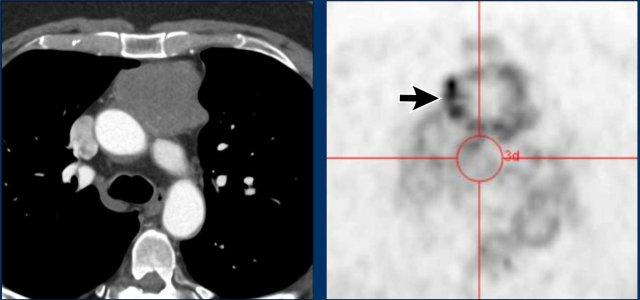

Các hình ảnh này của một phụ nữ 34 tuổi có triệu chứng khó thở.

Hãy phân tích các hình ảnh.

Nhận định của bạn là gì?

Hình ảnh

Có một khối nang ở khoang trung thất trước mạch máu.

Thành nang dày và có ngấm thuốc cản quang.

Do vẫn chưa rõ bản chất tổn thương, PET scan đã được thực hiện.

Tiếp tục xem các hình ảnh PET…

Dựa trên kết quả PET, chẩn đoán nào là có khả năng nhất?

Đây là u tuyến ức dạng nang, nang biến chứng, u thần kinh nội tiết hay u lympho?

PET cho thấy nhiều tổn thương, đây phải là các hạch bạch huyết bệnh lý.

Thảo luận

U tuyến ức hầu như không bao giờ đi kèm với hạch to.

Nang bị nhiễm trùng cũng có thể gây hạch to, nhưng không lan rộng như trong trường hợp này.

Chẩn đoán cuối cùng

U lympho dạng nang.